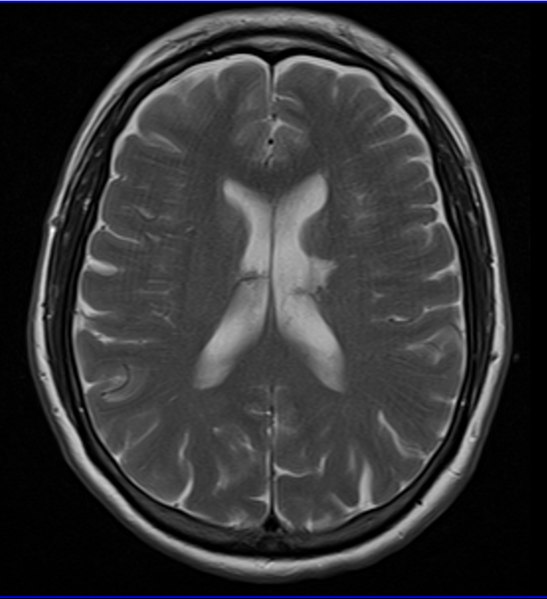

Si los síntomas indican que se ha producido un infarto lacunar, debe realizarse de inmediato una resonancia magnética o una tomografía computarizada. Esta última es necesaria para descartar una hemorragia intracerebral o un derrame cerebral.

El infarto lacunar se produce con mayor frecuencia en los ganglios basales, en la cápsula interna, en el tálamo, en la corona radiata y en la protuberancia. Es decir, estructuras subcorticales que están en la profundidad del cerebro.

– Ubicación profunda. Suele afectar estructuras como ganglios basales, cápsula interna, tálamo o tronco encefálico.